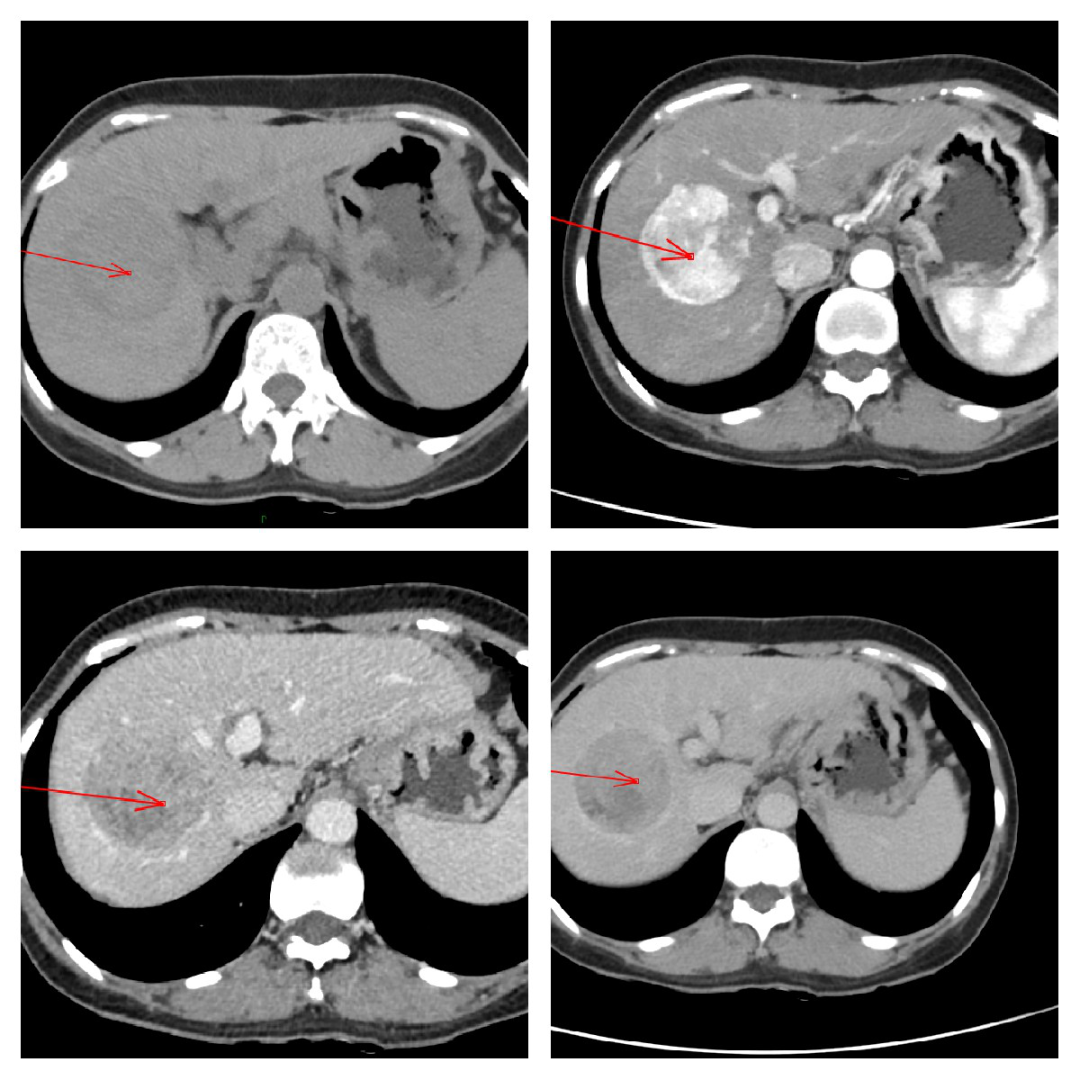

结肠癌肝转移:肝转移瘤一般在动脉期多发,呈「牛眼征」样强化,静脉期及延迟期继续为环形强化;通常与肝内胆管癌需要用 pet-ct、胃肠镜做鉴别诊断。

肝、胃间质瘤:胃肠比较容易出现间质瘤,肝往往为转移间质瘤;影像学特点是动脉期不均匀强化肿物影,与周围组织分界不清,向周围浸润。

肝脓肿:CT 动脉期环形强化,静脉及延迟期界限不清,伴发热,消炎后好转。